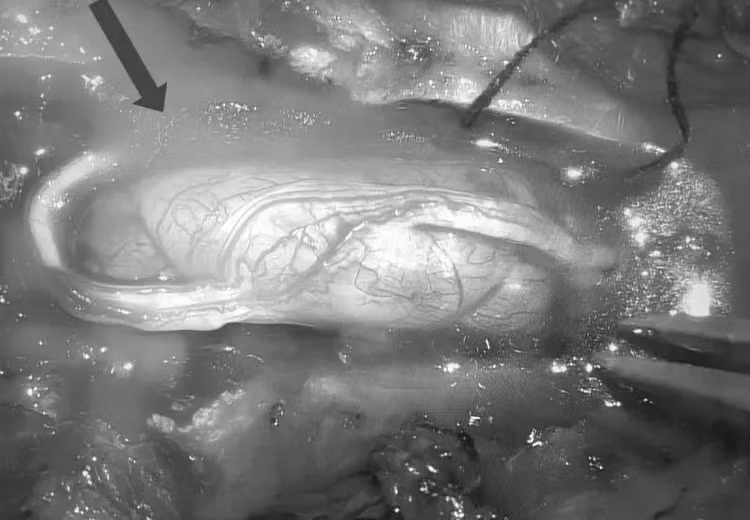

| Hình ảnh khối u tuỷ trong ống sống ngực đoạn ngang T6T7 kích thước (1,5 x 2 cm) của bệnh nhân. Ảnh BVCC |

Ngay sau khi phát hiện ra khối u, các bác sĩ đã thực hiện ca phẫu thuật lấy thành công khối u tuỷ trong ống sống ngực đoạn ngang T6T7 kích thước (1,5 x 2 cm) bằng kỹ thuật vi phẫu.

Cuộc phẫu thuật kéo dài 3 giờ đồng hồ, toàn bộ khối u đã được loại bỏ hoàn toàn.